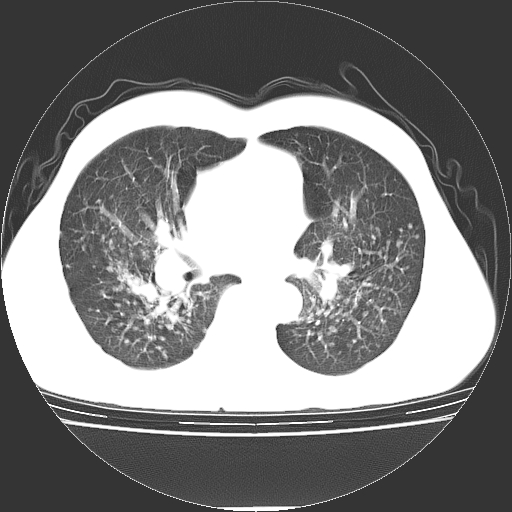

以下是引用yangyudong333在2008-4-29 5:38:00的发言:[br]比较典型的矽肺结节.支持[br]诊断依据:[br] 1.x线表现:[br] ①典型矽肺为多发直径 1~3mm 小结节,即矽结节,由胶原纤维和硅尘构成,可融合成团块,好发于上肺。[br] ②团块周围常有肺大泡。[br] ③胸内淋巴结增大、钙化。如肺门淋巴结呈蛋壳样钙化有助于与其他尘肺区别。[br] ④胸膜常广泛粘连、增厚。[br] 2.ct表现[br] ①两肺散在大小较为一致的小结节影,其密度较高,边界清楚。[br] ②小结节可融合为较大团块影,直径约 1cm ,甚至可达 10cm以上,易发生在上叶。[br] ③小结节周围常并有小叶中心气肿或弥漫性肺气肿。

以下是引用liuyue在2008-4-28 22:30:00的发言:[br]比较典型的矽肺结节.[br]请结合临床及化验除外矽肺合并肺结核之可能.